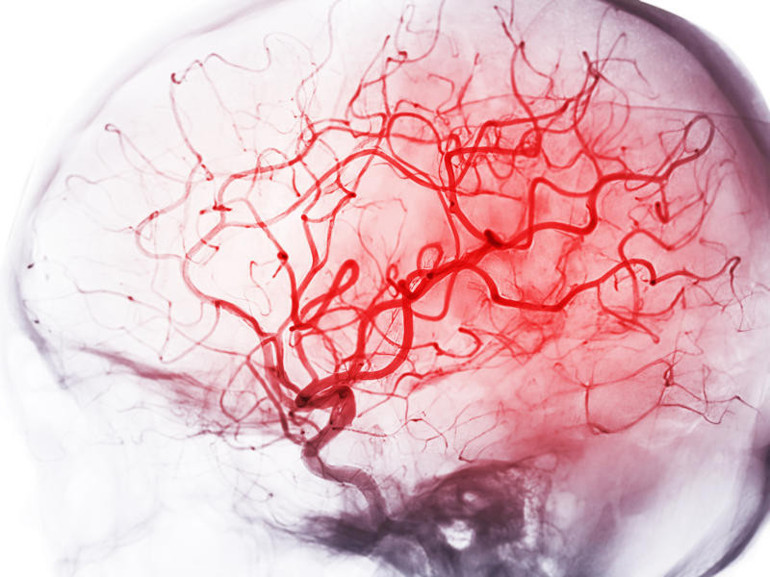

Kaynak: Daily Mailİnme, beyne giden kan akışının kesilmesi ve beyin hücrelerinin ölmesiyle meydana gelir. Hasar uzun süreli sakatlığa yol açabilir ve insanların düşünme ve hissetme biçimlerini etkileyebilir.En yaygın neden, iskemik inme olarak bilinen beyni besleyen arterleri tıkayan yağ birikintileri veya kan pıhtısıdır. Bu, kan damarlarının zamanla plaklar tarafından daraltıldığı veya tıkandığı kardiyovasküler hastalık nedeniyle olur. Bunlar, ateroskleroz olarak bilinen bir süreçte arter duvarlarında biriken kolesterol, kalsiyum ve diğer maddelerden oluşur.

Hemorajik inme olarak adlandırılan diğer atak türü ise beyinde bir kan damarı hasar aldığında ve kanı organa sızdırmaya başladığında meydana gelir.